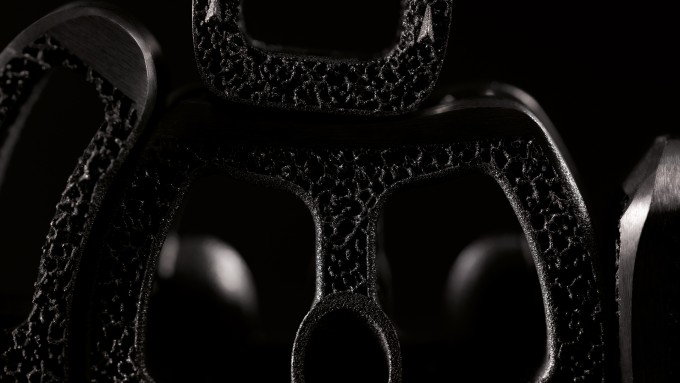

Nos cages Ti-LIFE présentent des surfaces polies à la main qui facilitent les procédures chirurgicales en assurant une insertion en douceur et en réduisant les risques de lésions des tissus mous et des nerfs. De plus, la technologie Ti-LIFE contribue à réduire le risque de (ré)infection, notamment contre les souches Gram+.

Nos cages Ti-LIFE sont polies à la main sur des zones spécifiques, comme l’extrémité biseautée, afin de faciliter l’insertion de l’implant, protéger les tissus mous et réduire le risque de complications peropératoires.